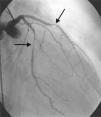

A 64-year-old white woman with a history of hypertension was admitted to hospital with new-onset chest pain consistent with angina. She had had multiple coronary angiograms (CA) four years previously for repeated episodes of typical chest pain and admissions. The CA showed non-obstructive coronary artery disease in the range of 40–50% in the left circumflex artery (LCx) which was confirmed to be non-obstructive by fractional flow reserve during the angiogram; no catheter-induced vasospasm occurred during the CA. Because of continued episodes of chest pain, she was taken off metoprolol and started on diltiazem 240mg once a day for possible vasospastic angina. She was then asymptomatic for the following four years, and also had a dobutamine stress echocardiogram, which was negative, about two months before the present admission for screening due to disease identified on her last CA. At this admission, she had new symmetrical anterolateral and inferior T inversion on the ECG consistent with ischemia; troponin levels were minimally elevated (0.3ng/ml). The patient had been seen by her primary care physician three days previously for a routine follow-up and was taken off diltiazem and started on nebivolol 10mg/day in addition to her medications of HCTZ 25mg and lisinopril 40mg/day, Lipitor 40mg, and enteric-coated aspirin 325mg/day for blood pressure (BP) control. In hospital she was started on nitro paste and intravenous (IV) heparin and her home medications continued. Because of continued chest pain in hospital and mildly elevated troponin I levels, she was scheduled for CA. She experienced chest pain at the beginning of the coronary angiogram, which initially revealed a 70% lesion and slow flow in the mid left anterior descending artery (LAD), a 90% lesion in the mid LCx and a 99% lesion in the ostium of the second obtuse marginal (OM2) (Figure 1, black arrow). The right coronary artery (RCA) had a distal 80–90% stenosis (Figure 2, black arrow). During preparation for percutaneous intervention in the LCx and OM2, intracoronary (IC) nitroglycerin was given for vessel sizing, after which there was resolution of the lesions in the LAD and decrease in the mid left LCx lesion to 50–60%, and resolution of the OM2 lesion, suggestive of significant reversible coronary artery spasm (Figures 3 and 4, white arrows). IC nitroglycerin was also administered in the RCA, in which lesion resolution was also seen. The coronary intervention was aborted, the patient's chest pain was resolved after IC nitroglycerin and she was started on IV nitroglycerin in the interim. Nebivolol was discontinued; diltiazem started in post-catheterization orders. She continued to have occasional episodes of chest pain for about 24hours after discontinuation of nebivolol. She was weaned from IV nitroglycerin the next day and started on oral isosorbide mononitrate. The following day the ECG changes resolved with no more episodes of chest pain; she was discharged home and was event-free in follow-up.